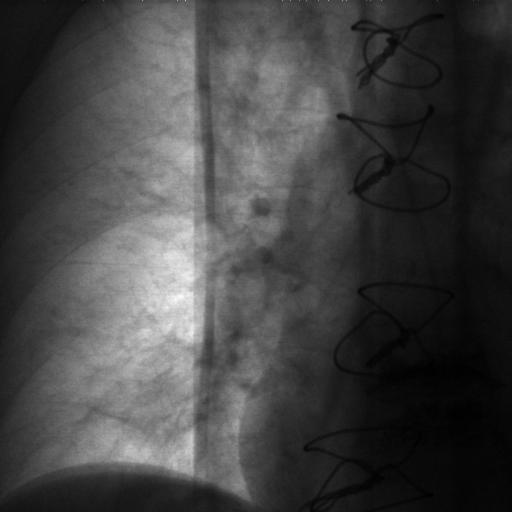

The dataset we use in the experiments is a cone-beam CT (CBCT) dataset captured for radiation therapy. The dataset contains 340 raw CBCT scans with each has 780 X-ray images. Each X-ray image comes with a geometry file that provides the registration ground truth as well as the information to reconstruct the CBCT volume. Each CBCT volume is reconstructed from the 780 X-ray images, and in total, we have 340 CBCT volumes (one for each CBCT scan). We use 300 scans for training and validation, and 40 scans for testing. The size of the CBCT volumes is 448×448×768448448768448\times 448\times 768 with 0.5 mm voxel spacing, and the size of the X-ray images is 512×512512512512\times 512 with 0.388 mm pixel spacing. During the experiments, the CBCT volumes are treated as the 3D pre-intervention data, and the corresponding X-ray images are treated as the 2D intra-intervention data. Sample X-ray images from our dataset are shown in Figure. Note that unlike many existing approaches [15, 17, 25] that evaluate their methods on small datasets (typically about 10 scans) which are captured under relatively ideal scenarios, we use a significantly larger dataset with complex clinical settings, e.g., diverse field-of-views, surgical instruments/implants, various image contrast and quality, etc.

We consider two common views during the experiment: the anterior-posterior view and the lateral view. Hence, only X-rays that are close to (±5°plus-or-minus5°\pm 5\degree) these views are used for training and testing. Note that this selection does not tightly constrain the diversity of the X-rays as the patient may be subject to movements with regard to the operating bed. To train the proposed method, X-ray and DRR pairs are selected and generated with a maximum of 10°10°10\degree rotation offset and 202020 mm translation offset. We first invert all the raw X-ray images and then apply histogram equalization to both the inverted X-ray images and DRRs to facilitate the similarity measurement. For each of the scan, we also annotate their landmarks on the reconstructed CBCT volume for further evaluation.

Refer to caption

Figure 6: Sample raw X-ray images of our dataset.